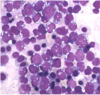

What disease is suggested by this peripheral smear?

Could be CLL (chronic lymphocytic leukemia) or peripheral blood involvement by SLL (small lymphocytic lymphoma)